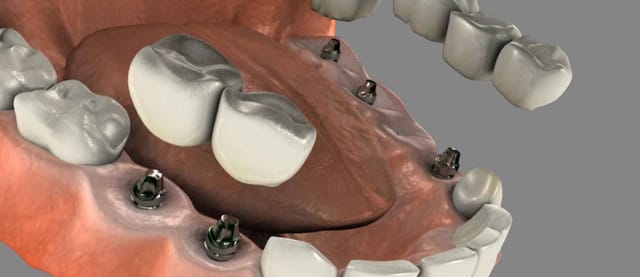

In many situations it is possible to remove the diseased and/or loose teeth and replace them with dental implants at the same time. This method of treatment reduces the number of surgical visits. It also speeds up the entire process enabling the implants to be ready to receive (caps/crowns) more quickly.

Once the implants are integrated with your bone, they can be used to support multiple crowns, a bridge, or secure a complete denture. Multiple tooth dental implants may be used to eliminate partial plates and dentures.